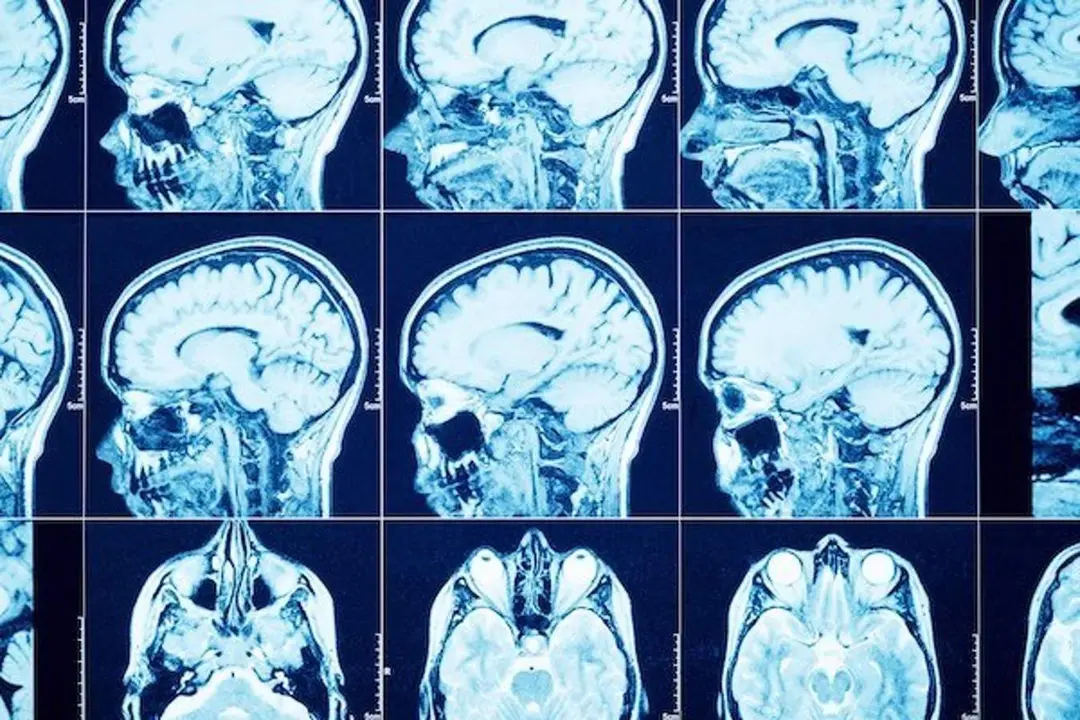

Los tumores cerebrales, una de las neoplasias más frecuentes en adolescentes

Los tumores cerebrales constituyen una de las neoplasias sólidas más frecuentes en adolescentes y adultos jóvenes (habitualmente a estas edades los más comunes son los gliomas de bajo grado) y, a partir de los 60 años, el tumor cerebral más frecuente es el conocido como glioblastoma multiforme o alto grado (aunque también lo encontramos a edades tempranas, pero con menor frecuencia), según señala la doctora Sara Cristina Gonzalez, del servicio de Oncología Médica del Hospital Universitario La Luz de Madrid.

Según la especialista, tradicionalmente, tanto el diagnóstico como el tratamiento de este tipo de tumores, han constituido un reto para la medicina y para la oncología en concreto, por su localización cerebral, lo cual dificulta el abordaje local de los mismos por el riesgo de generar secuelas neurológicas, y por la dificultad de alcanzar el sistema nervioso central con tratamiento de quimioterapia clásica ya que no todos los fármacos atraviesan con éxito la barrera hematoencefálica (la protección que tiene el cerebro de forma natural que impide el paso de sustancias tóxicas de la sangre a la circulación sanguínea cerebral).